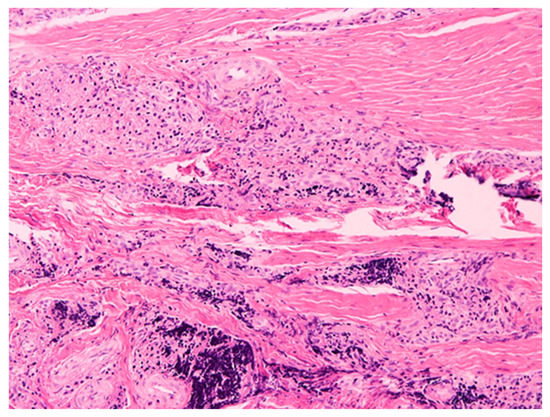

Pilot Study of Use of Nitric Oxide in Monitoring Multiple Dental Foci in Oral Cavity—A Case Report

by Magdalena Wyszyńska, Przemysław Rosak, Aleksandra Czelakowska, Ewa Białożyt-Bujak, Jacek Kasperski, Maciej Łopaciński, Nour Al Khatib and Małgorzata Skucha-Nowak

Healthcare 2022, 10(2), 195; https://doi.org/10.3390/healthcare10020195 - 20 Jan 2022

Background: The most common cause of implant loss and deteriorating restoration aesthetics is infection and chronic inflammation of the tissues around the implants. Inflammation in the oral cavity, confirmed by clinical and histopathological examination and determination of exhaled nitric oxide, is a situation [...] Read more.

Background: The most common cause of implant loss and deteriorating restoration aesthetics is infection and chronic inflammation of the tissues around the implants. Inflammation in the oral cavity, confirmed by clinical and histopathological examination and determination of exhaled nitric oxide, is a situation which may cause the complications on the whole human body. Elimination of the patology in the oral cavity in some cases is the only resonable treatment. The aims and objectives of our work is to present a gradual treatment of advanced infalmmation and present huge reduction stamp of inflammation measured with marker nitric oxide (NO) in exhaled air. Materials and Methods: Simple treatment containing elimantion of pathology in the oral cavity was conducted. Patient that came to the dental practice suffered from the inflammation caused by lack of proper hygiene. First aid in this situation was to eliminate the inflammation which may affect negatively for general health. At first visit full hygienization was performed, at the second visit roots of abutment teeth and implants were removed under local anesthesia along with cystic changes. Results: The hygiene precedures and extraction of the unsteady inflammationprosthetic restorations significantly decreased the level of NO in exhaled air. Conclusions: During the examination of the patient coming to the dental practice great attention should be paid to the coexistence of pathologies related to the oral cavity. Omission of a dental examination and possible elimination of odontogenic foci may affect the implication of the results of general diagnostics and subsequent treatment. Measuring the level of NO on exhaled air seems to be useful diagnostic method. Full article